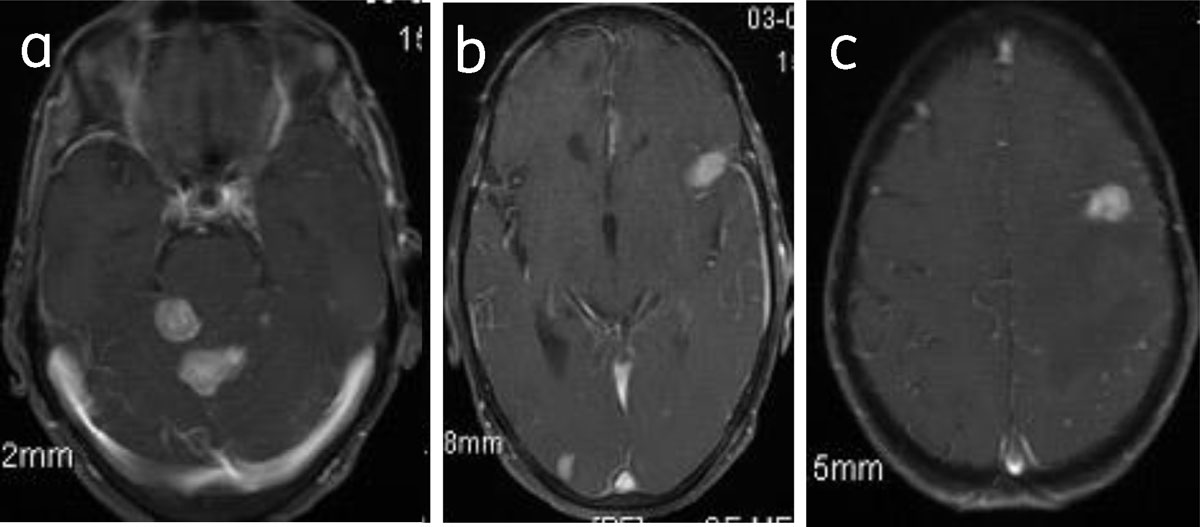

Multiple meningiomas are seen in association with neurofibromatosis 2 or multiple meningiomatosis syndrome [1] (Figure 15).

Figure 15

Meningiomatosis: Axial post-contrast (a, b, c) images show multiple enhancing meningiomas.